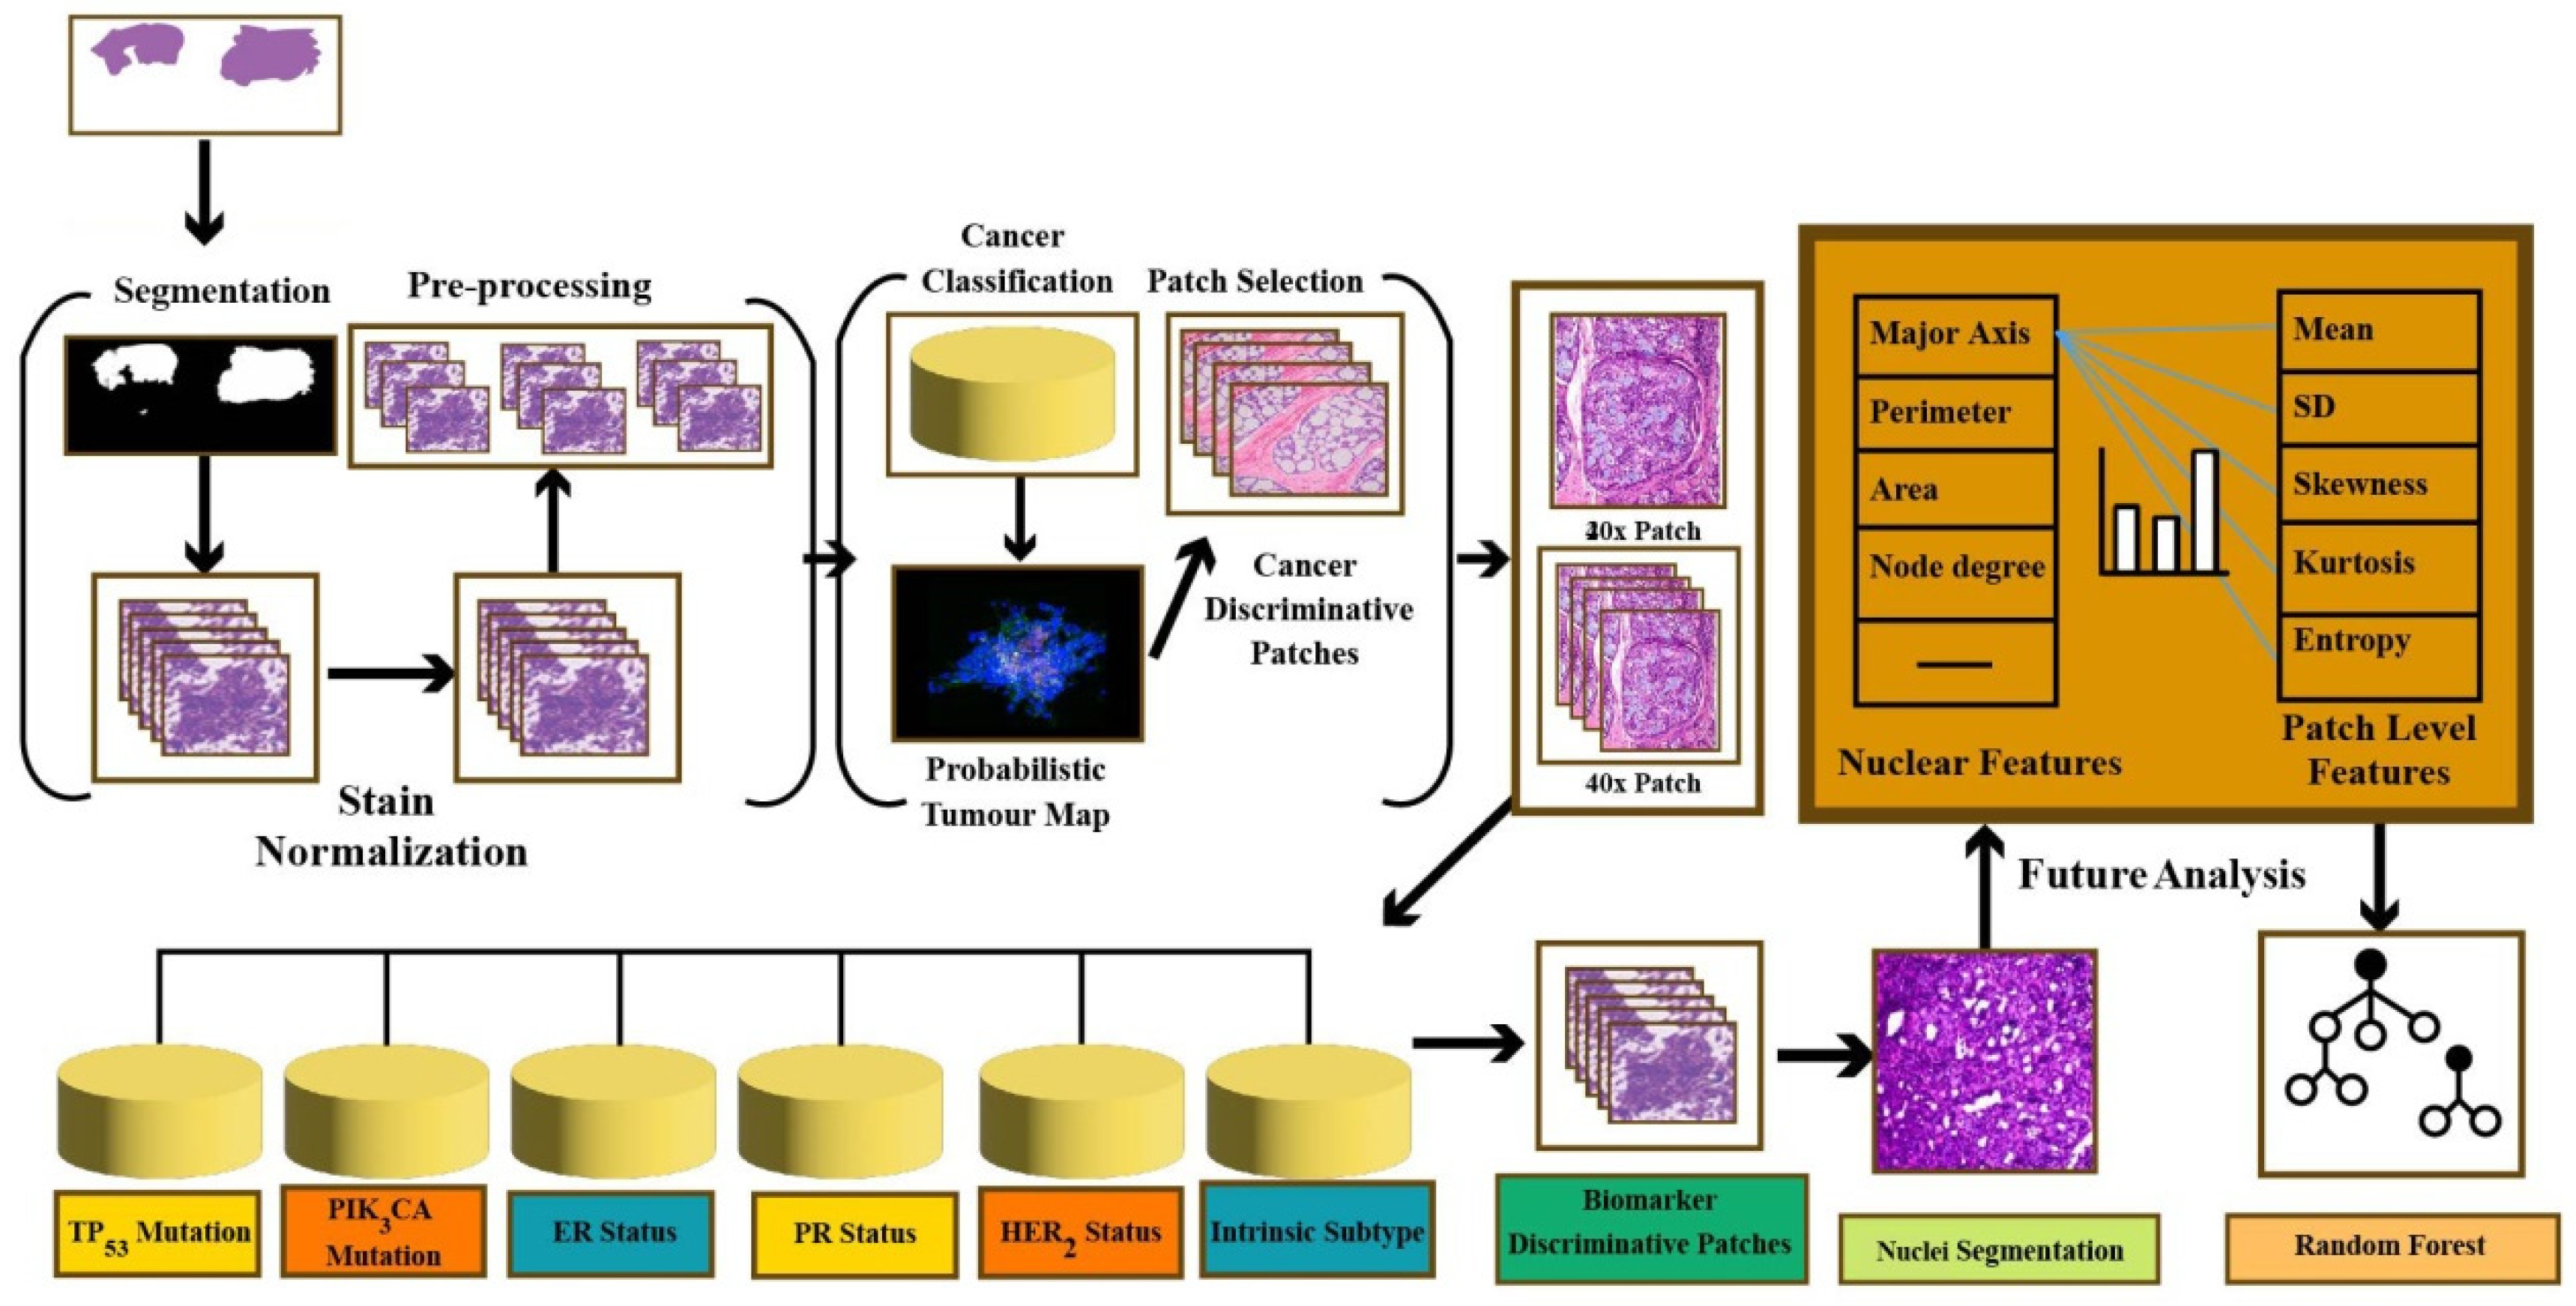

Data That Shows Early Detection Rather Than Late Detection In Breast Cancer

Build inspiration with our stunning architectural Data That Shows Early Detection Rather Than Late Detection In Breast Cancer collection of extensive collections of structural images. structurally highlighting photography, images, and pictures. perfect for architectural portfolios and presentations. Our Data That Shows Early Detection Rather Than Late Detection In Breast Cancer collection features high-quality images with excellent detail and clarity. Suitable for various applications including web design, social media, personal projects, and digital content creation All Data That Shows Early Detection Rather Than Late Detection In Breast Cancer images are available in high resolution with professional-grade quality, optimized for both digital and print applications, and include comprehensive metadata for easy organization and usage. Discover the perfect Data That Shows Early Detection Rather Than Late Detection In Breast Cancer images to enhance your visual communication needs. Cost-effective licensing makes professional Data That Shows Early Detection Rather Than Late Detection In Breast Cancer photography accessible to all budgets. The Data That Shows Early Detection Rather Than Late Detection In Breast Cancer archive serves professionals, educators, and creatives across diverse industries. Time-saving browsing features help users locate ideal Data That Shows Early Detection Rather Than Late Detection In Breast Cancer images quickly. Each image in our Data That Shows Early Detection Rather Than Late Detection In Breast Cancer gallery undergoes rigorous quality assessment before inclusion.